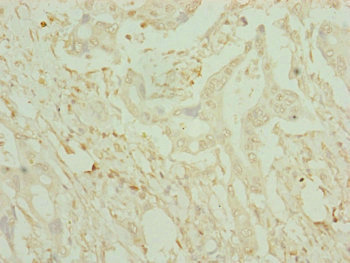

Immunohistochemistry of paraffin-embedded human liver cancer using CSB-PA621975ESR1HU at dilution of 1:100

Immunohistochemistry of paraffin-embedded human pancreatic cancer using CSB-PA621975ESR1HU at dilution of 1:100